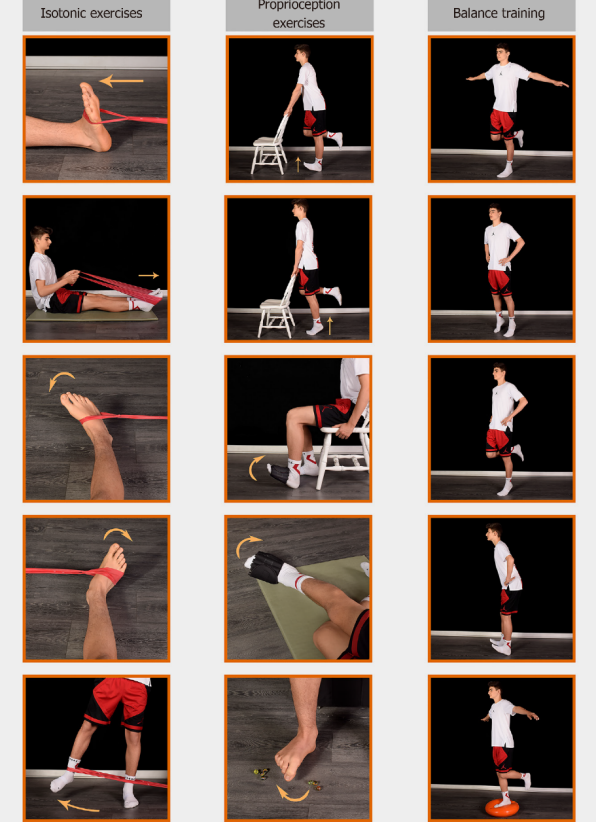

一文教你踝扭伤如何进行康复治疗,避免慢性踝不稳!

发布时间:2023-06-01分类: 浏览:145评论:0